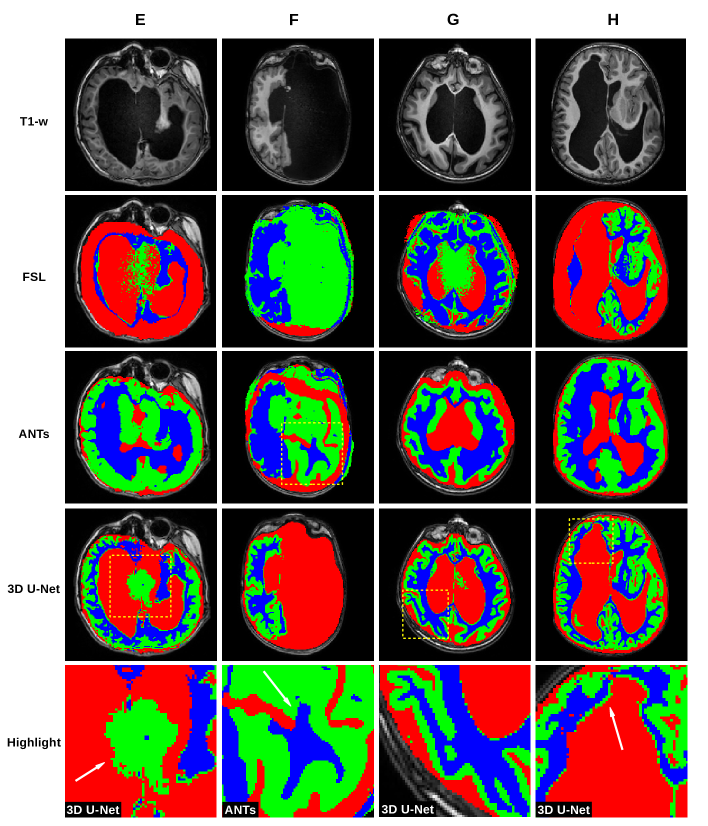

Complex distortions. 9 patients (average age 7.9 (SD=3.2)) with severe parenchymal distortion related to complex malformations (4 cases), parenchymal poroencephalic lesions and severe hydrocephalus (4 cases) and massive arachnoid cyst (1 case). See some cases in Figure 2.

In Figure 1, we show a paradigmatic set of axial slices segmented by FSL, ANTs and the 3D U-Net, from patients with ACC, i.e. from 4 of the 12 subjects described in Section 2.2. Similarly, in Figure 2, we report paradigmatic axial slices segmented by those methods, from 4 of the subjects with complex cerebral distortions. For the segmentations of all methods, we re-labeled as CSF all the voxels inside the brain mask of each patient that were incorrectly segmented as background. In both figures in the last row, for each subject, we highlight a detail of the slice for one of the segmentation methods (indicated with a dashed square, above in the same column). Such details are discussed in Section 5.

Figure 2 shows that, in case of complex malformations and severe parenchymal distortion, FSL and ANTs are unreliable and incur in major macroscopic errors, as opposed to 3D U-Net which performs vastly better. In cases of severe ventricular dilatation and distortion (E and H), FSL fails to segment the cortex, which is wrongly labelled as CSF. In case F, the CSF collection that replaces the left hemisphere is misclassified as the cortex. In G, FSL fails to properly segment the pachygyric (i.e. with a reduced number of gyri) cortex. Finally, some intensity inhomogeneities in the deep ventricular CSF are misclassified as GM (E and G). With ANTs, which is based on priors, the pipeline is forced to segment WM, GM and CSF in the missing hemisphere (F) or when the anatomy is highly irregular. In all of these cases, the pipeline misplaces structures (E, G, H) or segment structures that are actually missing (F). The 3D U-Net outperforms FSL and ANTs in all cases (e.g. G), with few mistakes. The main issues are: i) the mislabeling of signal inhomogeneities in the deep CSF (E, same as FSL), and the segmentation of a subtle layer of GM at the border between lateral ventricles and WM (H, as done in ACC cases). Care must be used in evaluating CSF/WM interface in cases of brain malformations because, at this level, heterotopic GM nodule may occur.